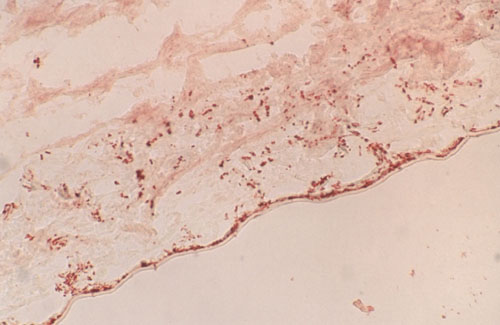

Figure 3. Cryosection of corneal tissue infected by Fusarium solani

Cryosection of corneal tissue infected by Fusarium solani (WGA, 5 mg/ml). In this section Fusarium solani fungi were located mostly in the area closest to Descemet membrane (x20).